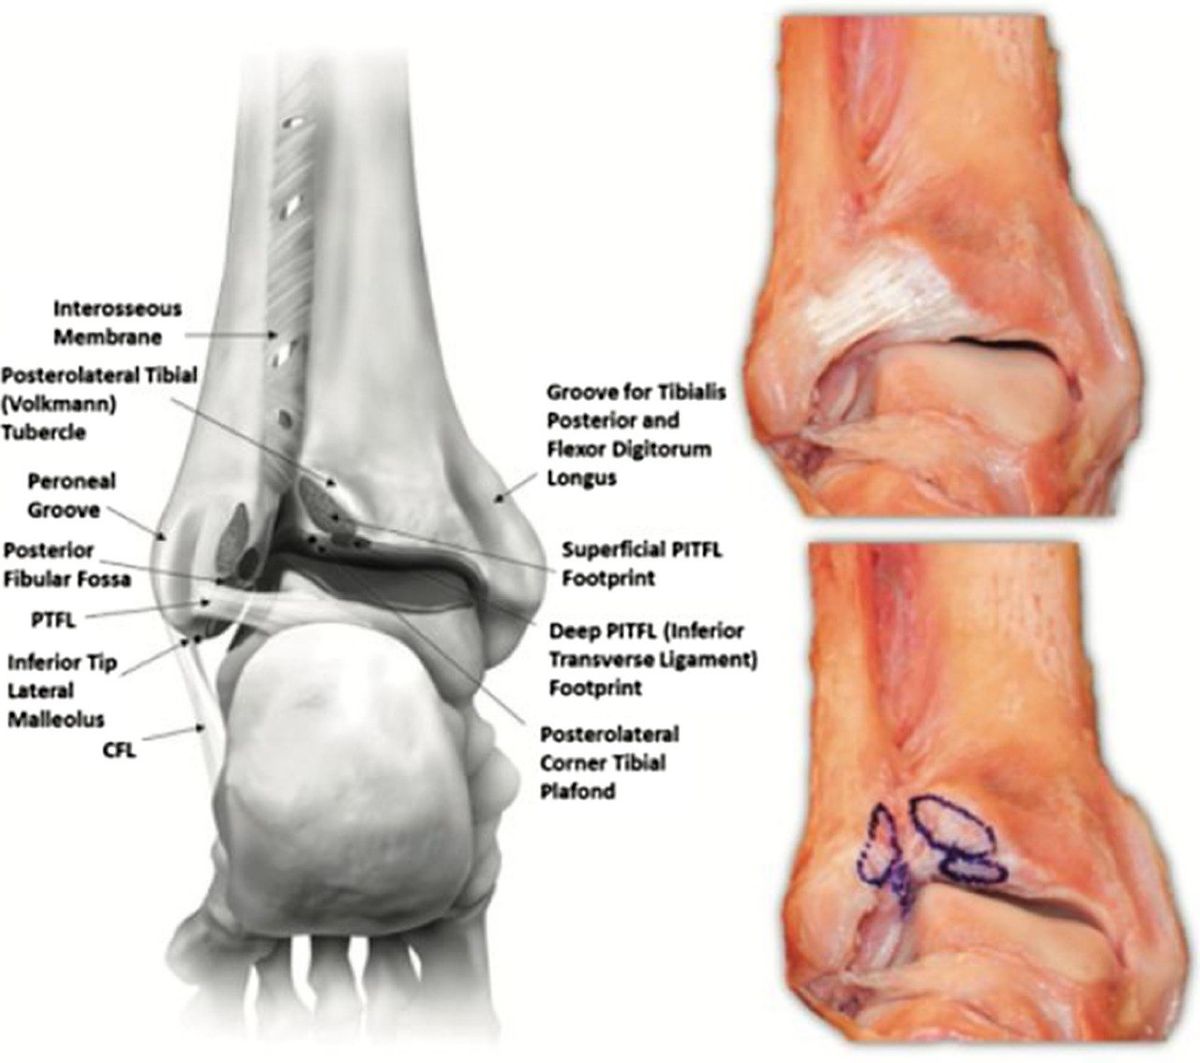

задняя нижняя большеберцово-малоберцовая связка (ЗНБМС, PITFL)

ЗНБМС — мощная связка, идущая от задней лодыжки большеберцовой кости к заднему бугорку малоберцовой кости в направлении от проксимально-медиального к дистально-латеральному. По форме и структуре она аналогична ПНБМс — мультифасцикулярна, состоит из множественных пучков коллагена с прослойками жировой ткани. Её нижняя часть, или поперечная связка (TTFL), расположена более горизонтально.

Поскольку ЗНБМС — толстая и прочная связка, чрезмерные нагрузки чаще приводят не к её разрыву, а к отрывному перелому задней лодыжки (фрагмент Фолькманна, Volkmann).

Рис. 8. задняя нижняя большеберцово-малоберцовая связка (ЗНБМС/PITFL), вид сзади. 3D-модель и кадаверные препараты. Два пучка: поверхностный и глубокий (нижняя поперечная связка). Трапециевидная форма, толщина 6 мм, длина 20 мм. Площадка прикрепления на малоберцовой кости — 26,3 мм от верхушки, на большеберцовой — 9 мм.

Поперечная межберцовая связка (TTFL)

Поперечная связка проходит горизонтально между проксимальным краем лодыжковой ямки малоберцовой кости и задненижним краем большеберцовой кости, иногда достигая задней поверхности внутренней лодыжки. Это толстая округлая связка, которая углубляет задненижний край большеберцовой кости и формирует аналог суставной губы (labrum analogue). Часть волокон задней таранно-малоберцовой связки (PTFL) сливаются с наиболее дистальными волокнами поперечной связки, образуя так называемый tibial slip, или межлодыжковую связку (IML).

Межлодыжковая связка (IML)

Межлодыжковая связка — отдельная анатомическая структура, обнаруживаемая почти всегда — в 81,8% из 77 препарированных образцов. IML начинается чуть проксимальнее начала задней таранно-малоберцовой связки в лодыжковой ямке и дистальнее начала поперечной связки. Она идёт параллельно поперечной связке, но всегда отделена от неё треугольным или четырёхугольным пространством, заполненным мягкими тканями.

При подошвенном сгибании IML расслабляется и приближается к поперечной связке. Пространство между поперечной связкой и IML делает заднелатеральный доступ при артроскопии голеностопного сустава наиболее безопасным с точки зрения сохранности связочных структур. IML может быть причиной заднего импинджмента у балерин — при крайнем подошвенном сгибании возможно её ущемление или формирование повреждения по типу ручки лейки.

Также в области проксимальной части межберцового синдесмоза может проходить ветвь малоберцовой артерии, которая формирует анастомоз с большеберцовой артерией. В ряде случаев данная ветвь имеет большой диаметр и её повреждение при установке позиционного винта может вызывать сильное кровотечение.

Рис. 10. Варианты расположения сосудов в области межберцового синдесмоза